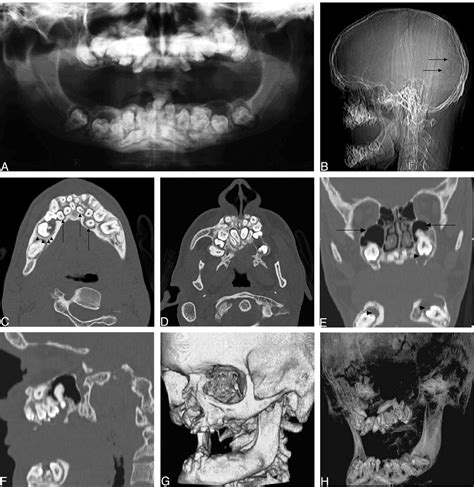

CT Scan Very High Provides detailed, cross-sectional views; excellent for complex fractures.

X-ray (Radiography) High for fractures Fast, readily available, inexpensive.